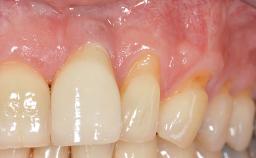

Connective-Tissue Graft to Increase the Width of the Keratinized Mucosa Around an Osseointegrated Implant

Adequate peri-implant soft-tissue thickness is essential not only for esthetic but also for functional reasons. In this case, Vincenzo Iorio Siciliano demonstrates how he achieved increased height and thickness of posterior peri-implant soft tissues to obtain a stable mucosal seal and a width of keratinized tissue favorable to toothbrushing.

The patient, a healthy 38-year-old woman, was referred for increasing the width of the keratinized tissues at the buccal aspect of dental implant 46. The site exhibited a premature-closure screw exposure caused by trauma during chewing, with inadequate keratinized tissue.